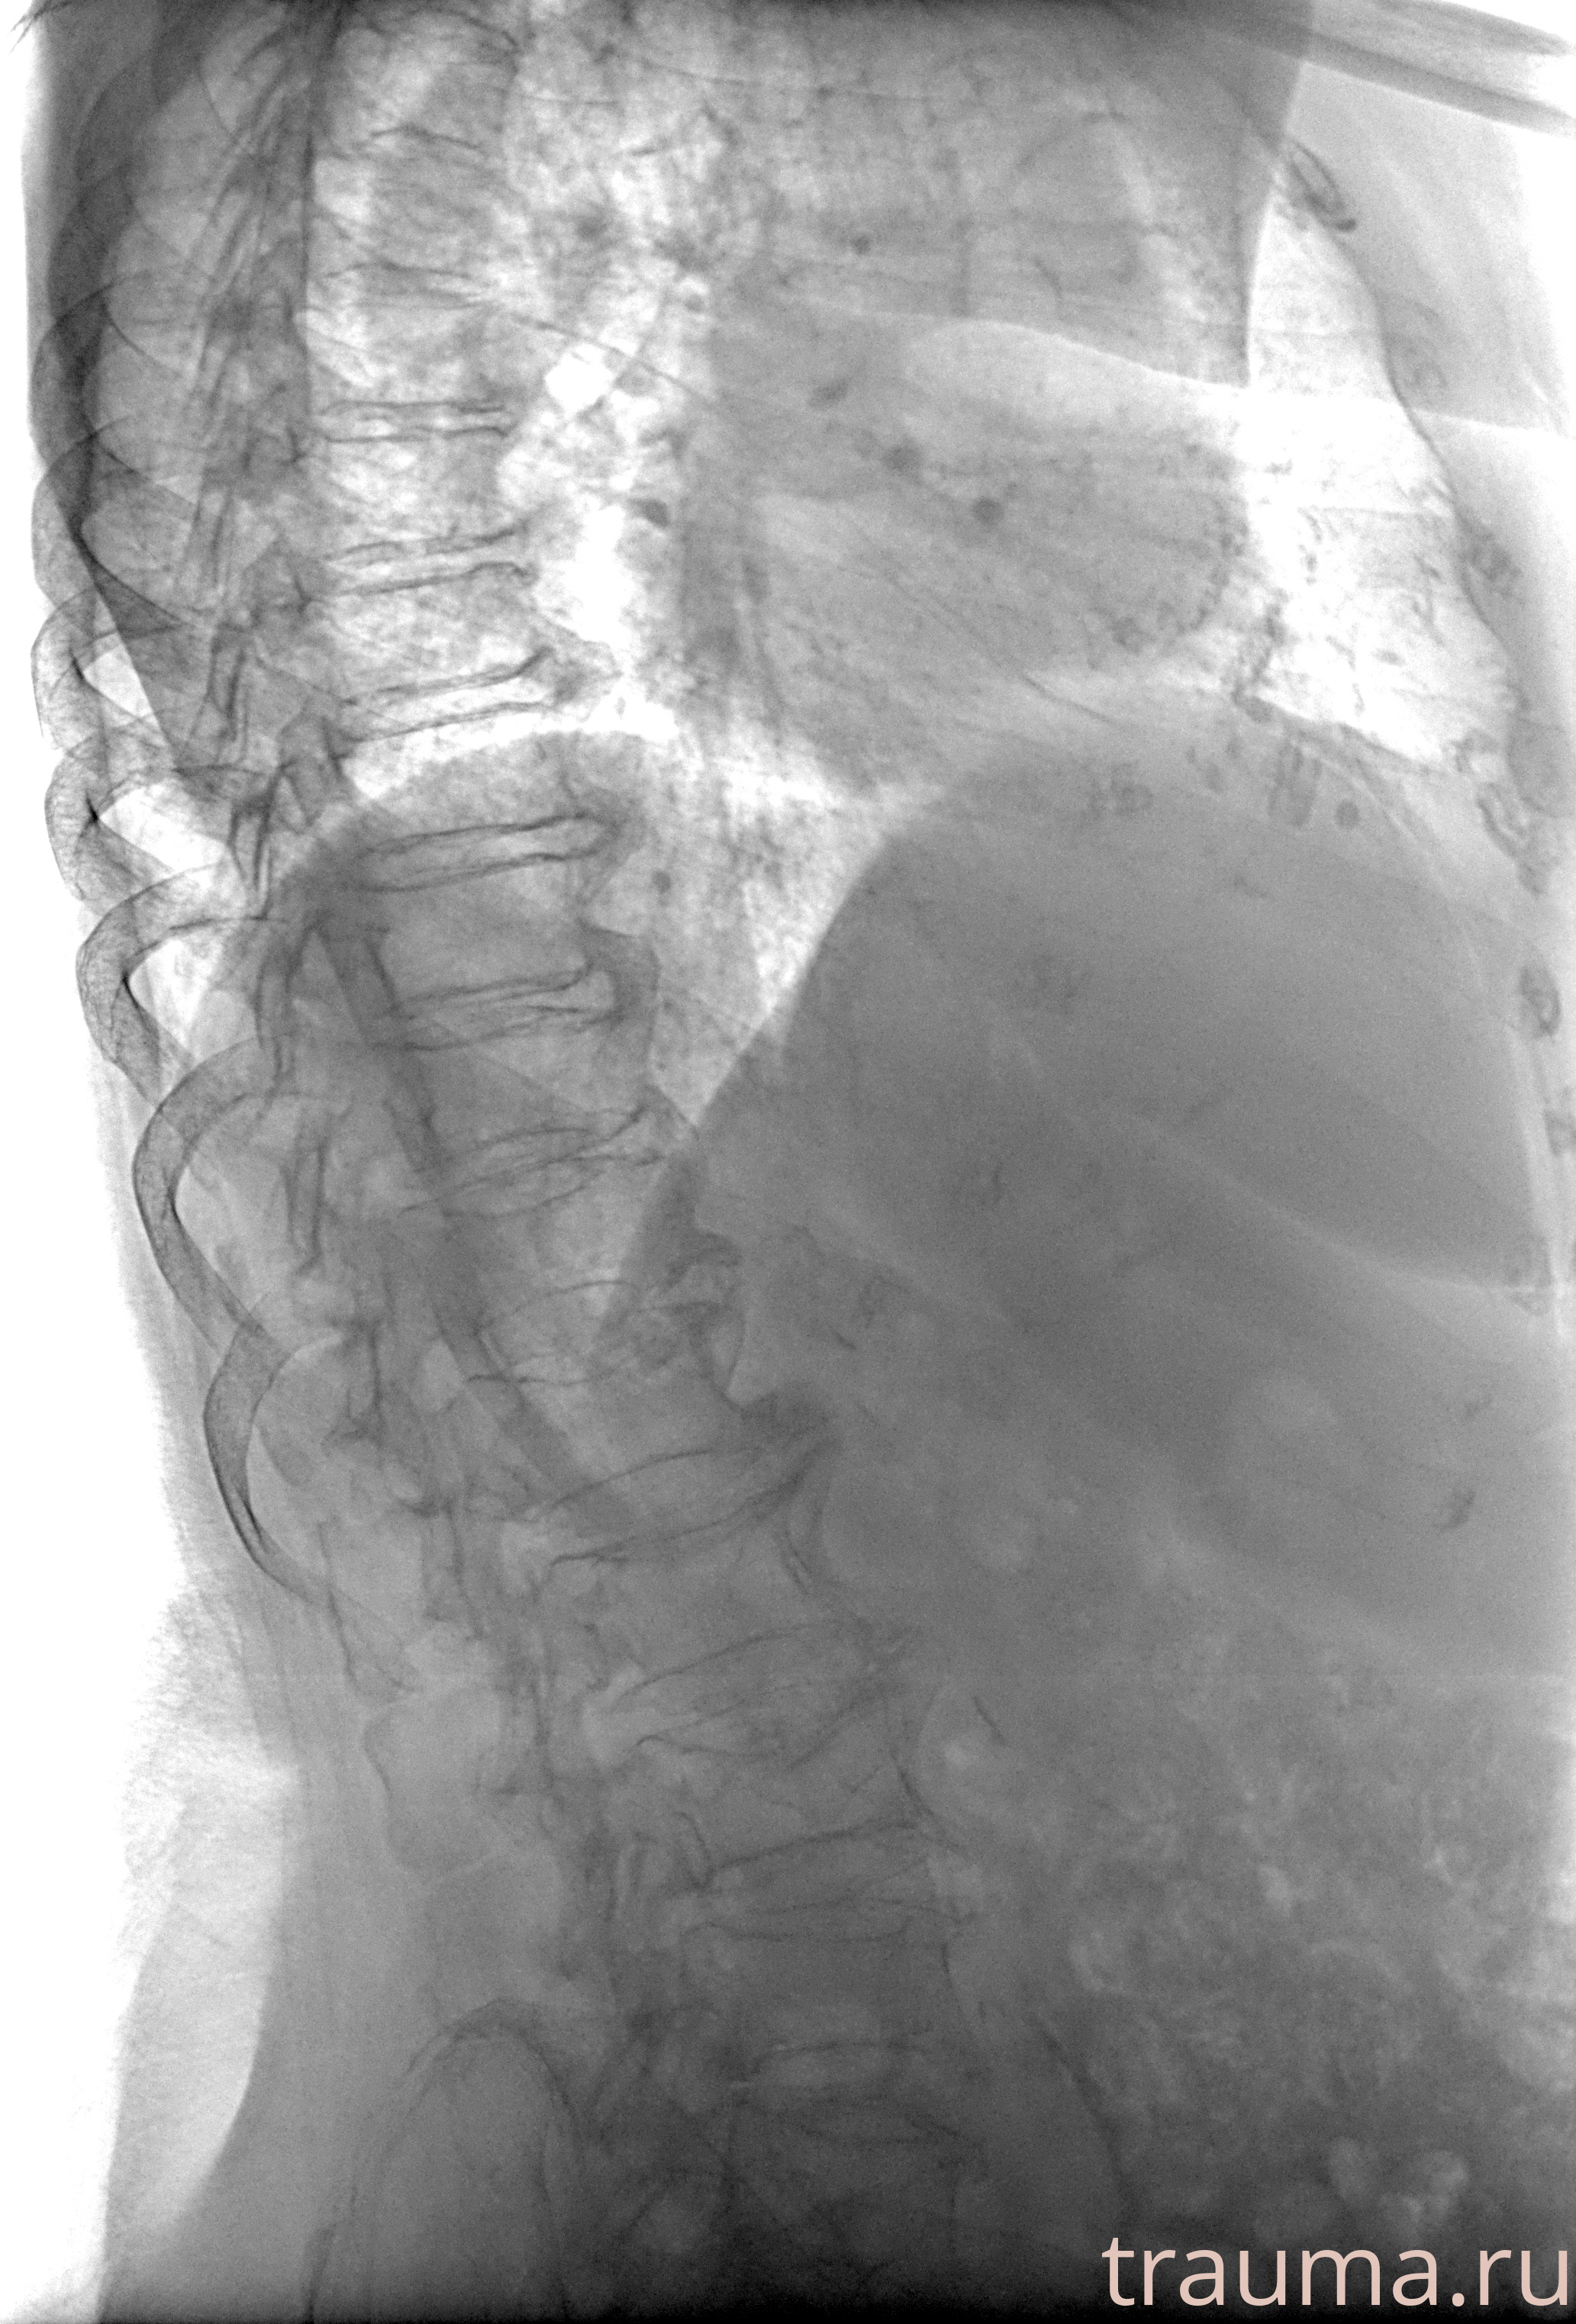

Рентгенограммы

Рентген на дому: по вашему адресу приезжает врач-рентгенолог, травматолог-ортопед с мобильным рентгеновским аппаратом, проводит диагностику травмы или заболевания, делает необходимые рентгенограммы, дает рекомендации по дальнейшему лечению. Получить качественные снимки в домашних условиях возможно благодаря уникальной методике, разработанной МосРентген Центром для института  Склифосовского

при переломе шейки бедра и пневмонии от компании МосРентген Центр - партнера Института имени Склифосовского